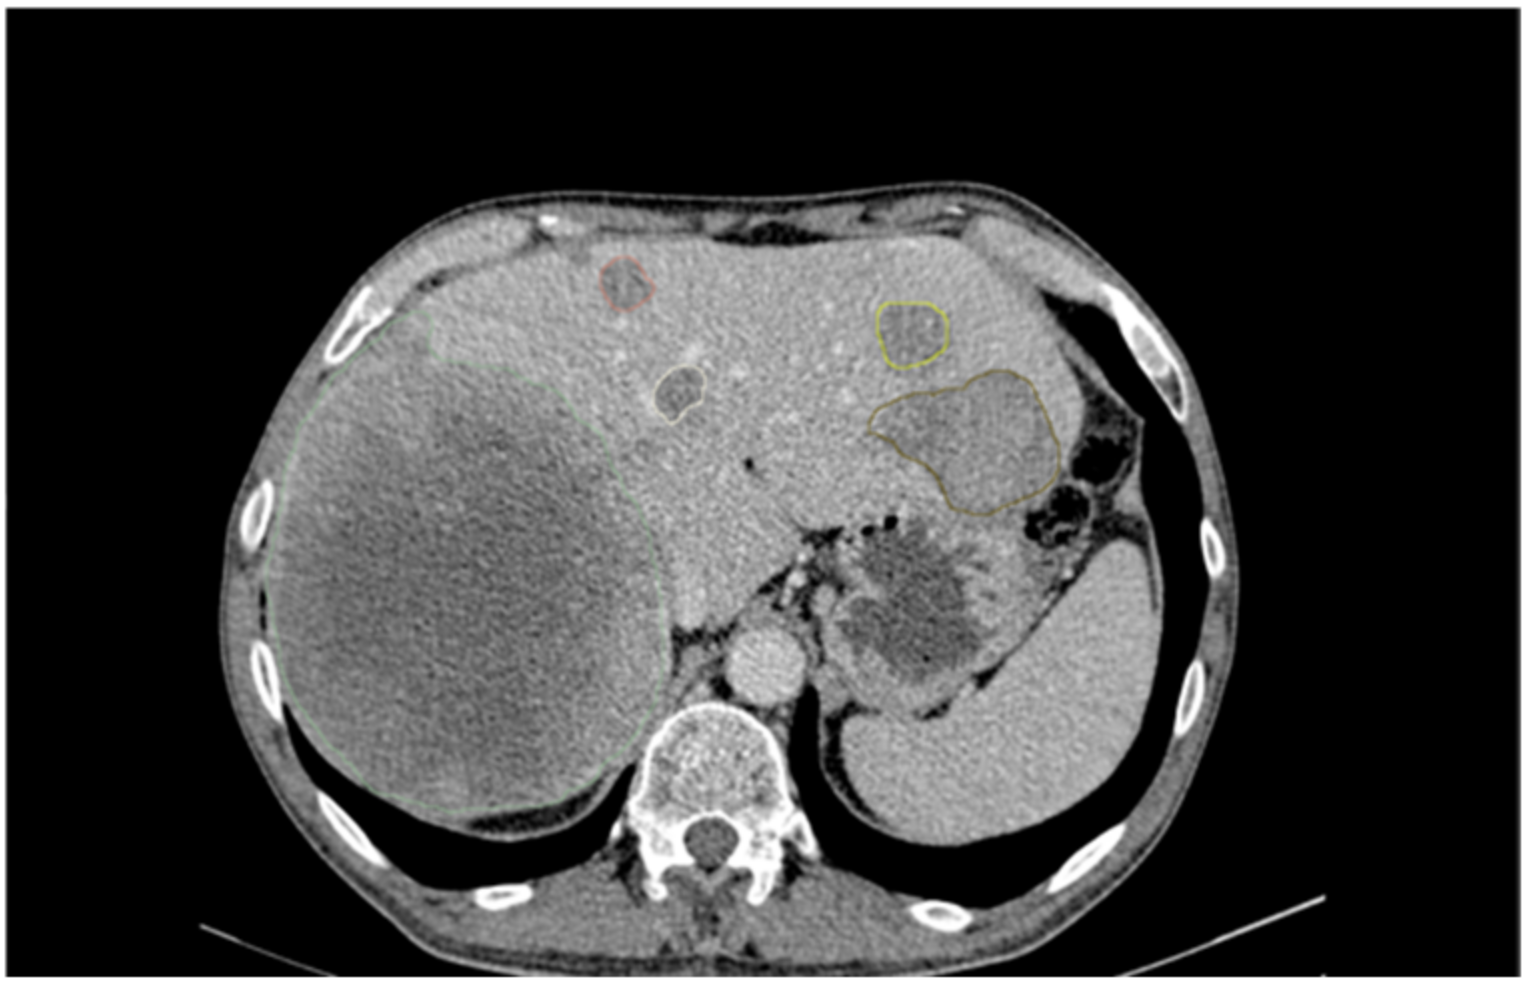

2.2. Image Analysis and Segmentation

3.5. Visual Cluster Analysis